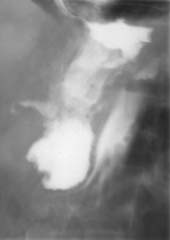

Рис. 1. По дренажной трубке в свищевой ход введено контрастное

вещество (Слева). В толстую кишку (per rectum) введен воздух

(Справа). В просвете толстой кишки определяется контраст,

что свидетельствует о наличии толстокишечного свища.

1. Сочетание фистулографии урографином с пневмоколоноскопией (раздувание толстой

кишки воздухом) у больного Я., 25 лет, находившегося на стационарном лечении

в хирургии с длительно незаживающим свищом после пулевого ранения брюшной полости,

позволило диагностировать перфорацию нисходящего отдела ободочной кишки, поддерживающую

гнойно-воспалительный процесс в брюшной полости. Точная локализация перфоративного

отверстия (места, где контраст через свищевой ход попал в просвет толстой кишки

на фоне ее раздувания воздухом) позволило квалифицированно устранить причину

нагноительного процесса и обеспечить выздоровление пациента (Рис. 1).